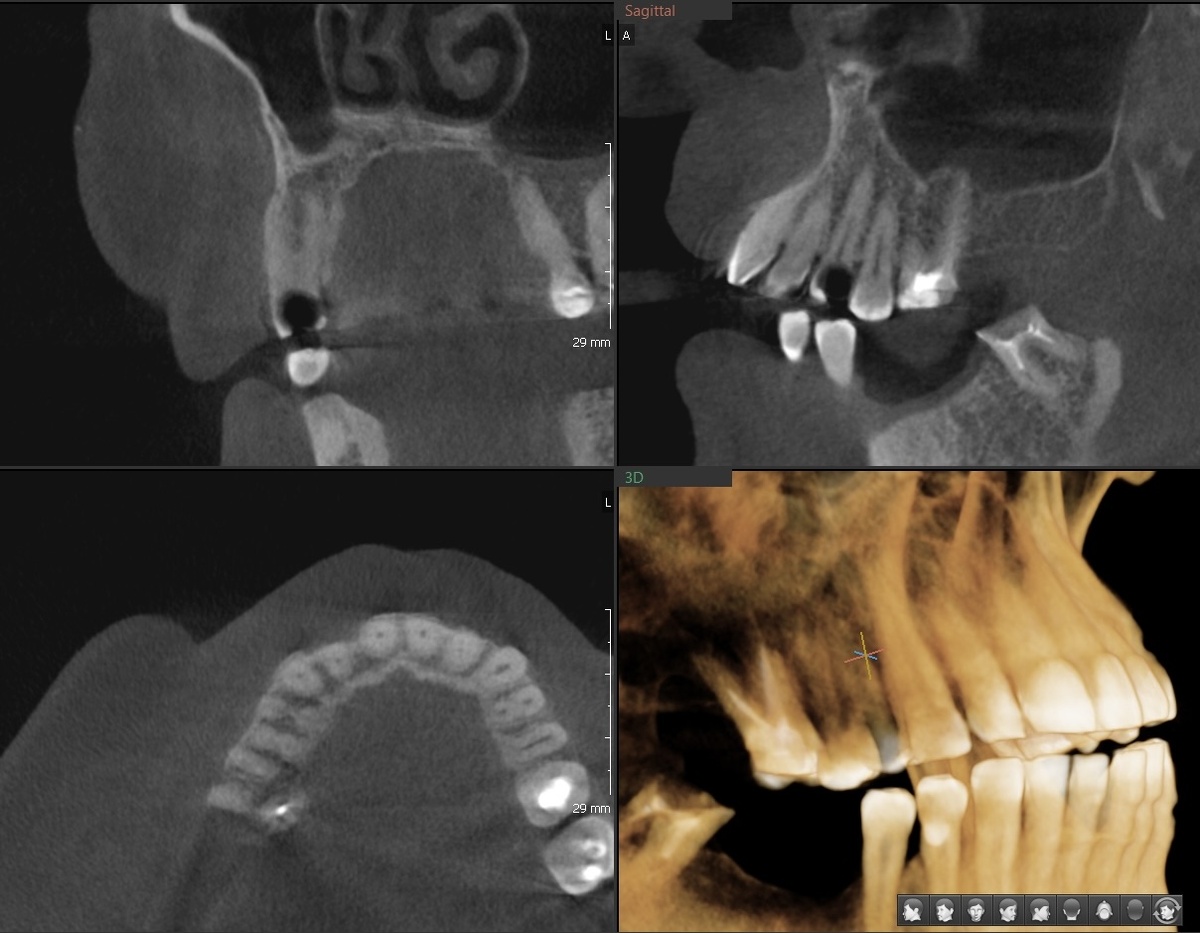

Пульпит 1.4 зуба

Картина ещё печальнее - от зуба остались рожки да ножки. Но корни целые, на рентгене никаких проблем нет. Значит, будем спасать.

Ну и пломбировка каналов на рентгеновском снимке:

-9